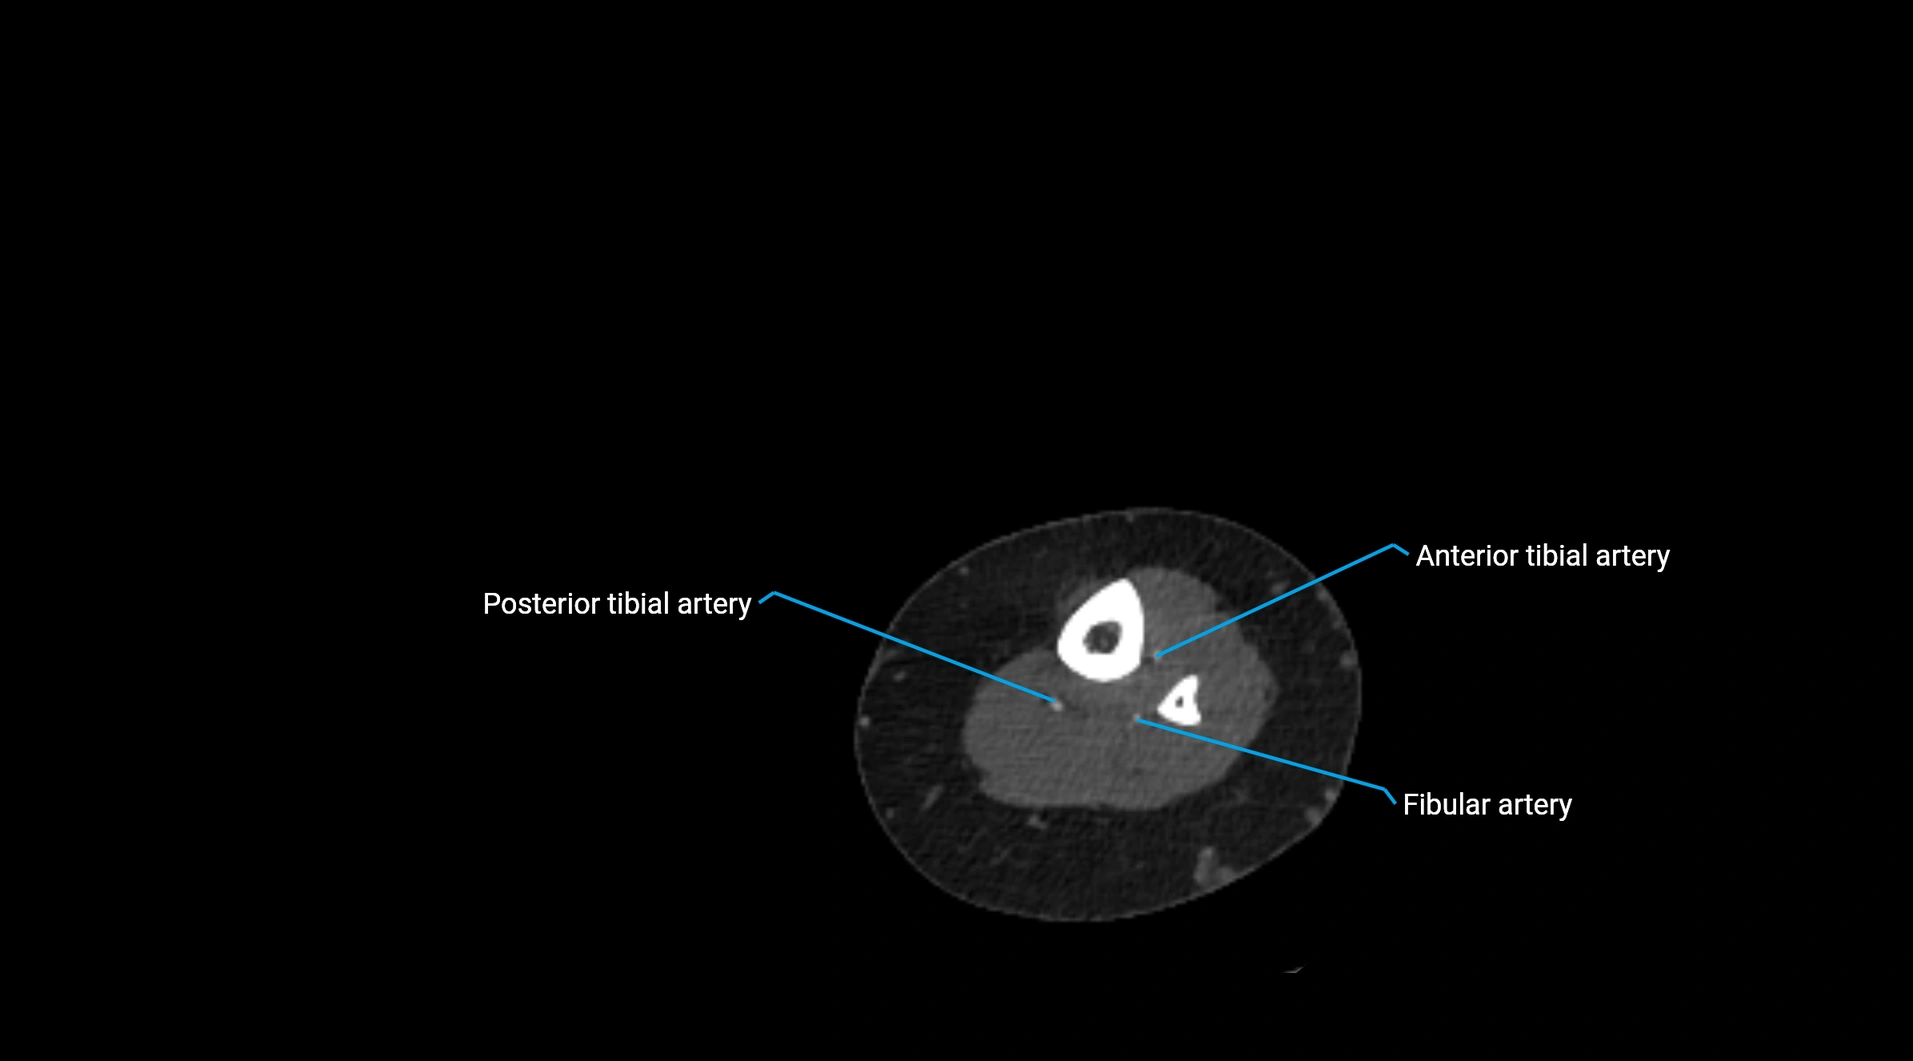

CT images

image

Contrast-enhanced CT (CTA):

• Gold standard for abdominal aortic imaging

• Provides excellent detail of lumen, wall, aneurysm, thrombus, and branch vessels

• Multiplanar and 3D reconstructions help in aneurysm measurement, stent graft planning, and dissection evaluation

• Detects acute rupture, traumatic injury, or occlusion with high sensitivity